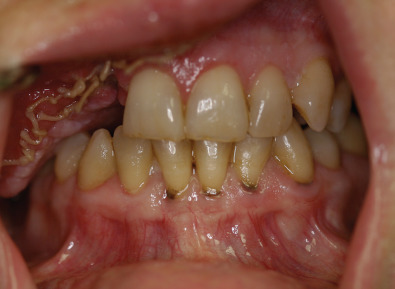

It is also important for those involved in treatment to be able to recognize the oral pathology resulting from poor oral health status. For example, advanced periodontal disease, gross dental caries, and excessive plaque and calculus formation are indicators of poor oral hygiene. These findings should be noted when referring the patient to the clinician who will perform a thorough radiographic and dental examination. Commonly in trauma patients previous dental casts are not available, so this examination may include acquisition of impressions from dental and facial structures as needed. The casts fabricated from these impressions can be used as aids in the treatment planning and posttreatment rehabilitation. Furthermore, the identification of hopeless teeth (i.e., severely decayed, extensive fractures) that need to be extracted will be made as well as weighing the need for any restorative treatments. Assessment of available soft and hard tissue can also be done at this appointment and, if possible, further advance imaging is obtained to evaluate available bone for future placement of osseointegrated dental implants.

If reconstruction using free tissue flaps is planned, an attempt should be made to keep the flap from being too bulky, as this extra tissue will require subsequent surgical revisions to allow proper space for the fabrication of a prosthesis ( Figs. 3.11.1 and 3.11.2 ).